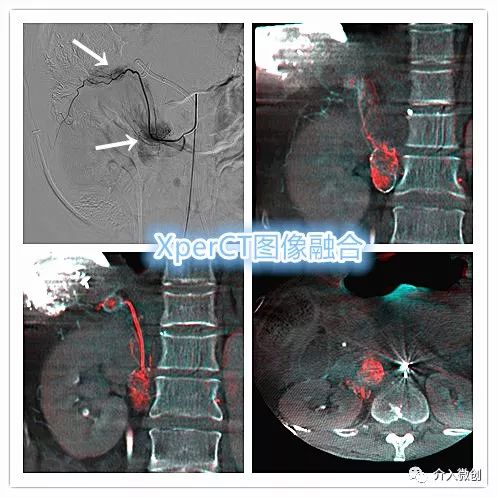

术中DSA造影提示腰动脉分支供血肿大淋巴结及肝脏肿瘤病灶下缘,术中行XperCT检查,融合CT与DSA血管造影图像,确认与术前CT提示病灶吻合,遂精确插管到位行化疗栓塞治疗,有效杀灭控制肿瘤病灶。